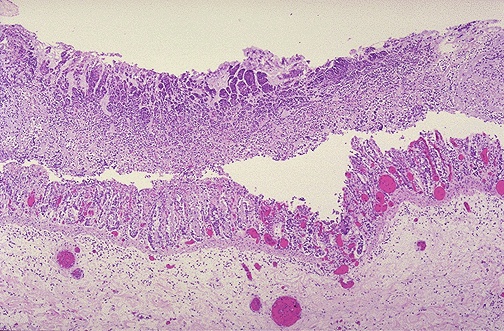

Image 3.3

At low power microscopically, the colon shows surface mucosal erosions with overlying

fibrinopurulent exudate

.